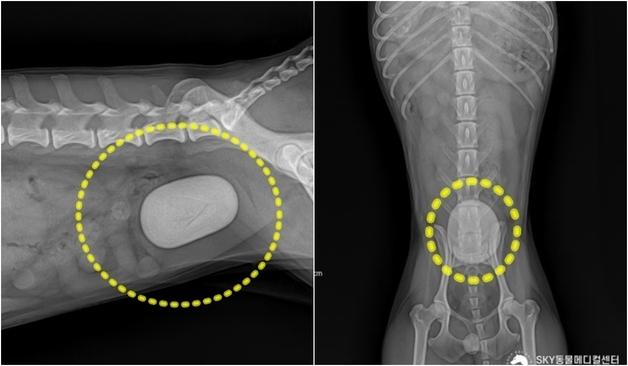

소생 가능성이 없다는 판단을 받았던 11살 '짜장이'. 급성 췌장염에서 시작된 병은 급성 신부전으로 악화했고 담낭 파열까지 의심되는 상황이었다. 여러 병원을 거쳤지만 "사실상 치료가 어렵다"는 설명이 이어졌다. 보호자는 마지막이라는 심정으로 한 동물병원을 찾았다.당시 제시된 생존 확률은 약 7~8%. 일반적으로 이 상태라면 적극적인 치료보다 가족과의 마지막 시간을 준비하도록 권유하는 경우가 많다. 하루 이틀 내 사망 가능성까지 언급된 상황이었다